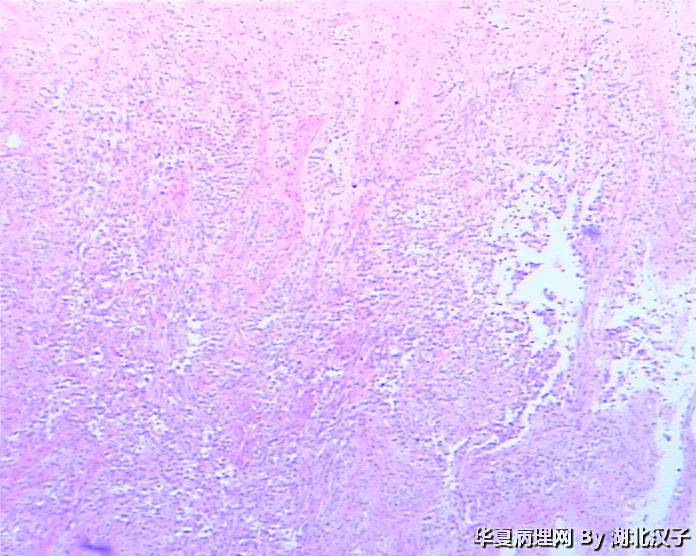

48岁,宫颈肿物